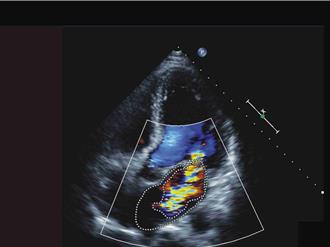

不是感冒! 6旬果農高燒、心臟有雜音 竟染心內膜炎敗血還化膿

彰化1名68歲的陳姓果農,去年底因發燒就診,本以為是感冒,然近日他突又發燒40度,且有寒顫、低血壓等狀況,並感到食慾喪失及全身無力,經詳細看診,被發現其心臟有異常雜音,進一步檢出罹患致死率近四成的感染性心內膜炎,幸好在進行微創二尖瓣人工瓣膜置換術後,症狀獲得控制。